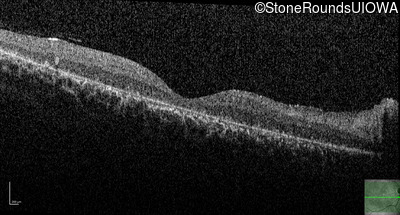

This 14 year old male began having trouble reading before the 1st grade. His parents noticed that he would not look directly at anyone.

| AR Stargardt Disease | ABCA4 | Ala1038Val GCC>GTC / Leu541Pro CTA>CCA | IVS36+3 del4tAAGT | AR |